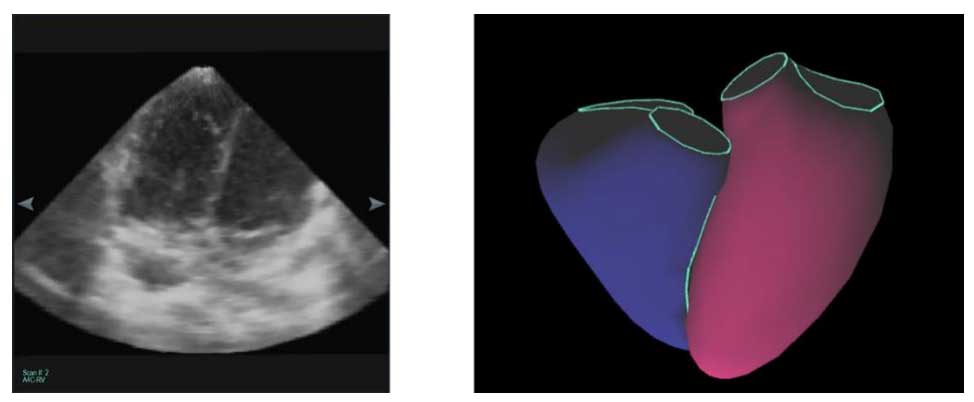

The VMS+ for 3D echo system offers a significant leap in efficiency by requiring only one 3D echo whole-heart scan to provide comprehensive volumetric data.

Unlike standard real-time 3D echo (RT3DE) methods that may require multiple acoustic windows or complex multi-step acquisitions, VMS+ for 3D utilizes a single “full-volume” dataset

to reconstruct the cardiac chambers. This approach is not only faster but also significantly more comfortable for patients, as it minimizes the time needed for probe manipulation and breath holding. By matching endocardial landmarks against a validated library of heart shapes, VMS+ provides reliable, non-invasive measurements that match the accuracy of cMRI. “KBR is an accurate, versatile, and time-saving method for right ventricular three-dimensional volumetry; it shows excellent reproducibility for RT3DE and CMR data sets.”*

The VMS+ Solution VMS+ overcomes this weakness by utilizing a proprietary KBR algorithm based on landmark-detection. By leveraging a validated MRI database of both normal and

pathological heart morphologies in adults and pediatrics, the system can calculate volumes with cMRI-equivalent accuracy across all four heart chambers—from just one 3D scan. This vendor-neutral analysis package ensures that regardless of the ultrasound hardware used, your data is accurate, reproducible, and ready for immediate clinical application.